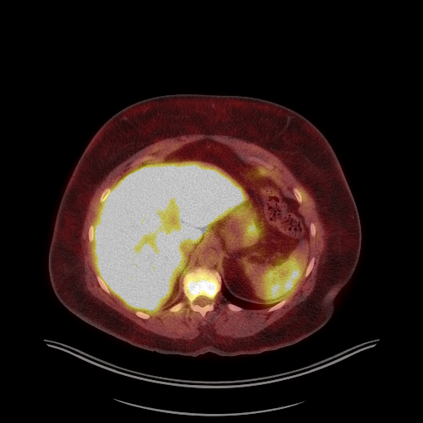

Medical images play a crucial role in assisting diagnosis, remote consultation, and academic research. However, during the transmission and sharing process, they face serious risks of copyright ownership and content tampering. Therefore, protecting medical images is of great importance. As an effective means of image copyright protection, zero-watermarking technology focuses on constructing watermarks without modifying the original carrier by extracting its stable features, which provides an ideal approach for protecting medical images. This paper aims to propose a fragile zero-watermarking model based on dual quaternion matrix decomposition, which utilizes the operational relationship between the standard part and the dual part of dual quaternions to correlate the original carrier image with the watermark image, and generates zero-watermarking information based on the characteristics of dual quaternion matrix decomposition, ultimately achieving copyright protection and content tampering detection for medical images.